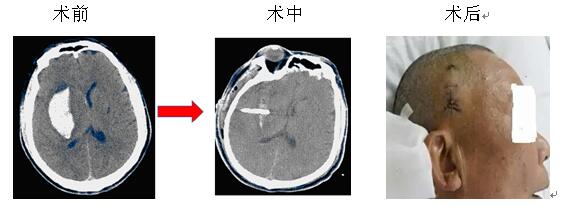

微創(chuàng)治療腦出血是指在CT或立體定向引導(dǎo)下,找到離血腫中心最近的位置,同時(shí)避開(kāi)重要的組織,用YL-I型針管一體裝置在電驅(qū)動(dòng)下安放引流管、抽吸血凝塊,減少血腫體積,達(dá)到清除血腫的目的。此方法創(chuàng)傷微小,操作快捷,費(fèi)用較低,在有CT的醫(yī)療器械情況下即可實(shí)施,故對(duì)廣大病患,特別是老年多病的腦出血患者而言是一種不二的選擇。

院神經(jīng)內(nèi)科率先在衡陽(yáng)地區(qū)實(shí)施微創(chuàng)治療腦出血,現(xiàn)經(jīng)救治的病患已達(dá)3000余人次,絕大部分患者得到好的結(jié)果,較少的死亡率,較輕的致殘率。本院將繼續(xù)提供較好的治療和服務(wù),來(lái)滿足病友的需求,也歡迎病友垂詢。